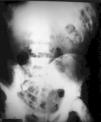

Varón de 82 años con estupor

82 year old male with stupor